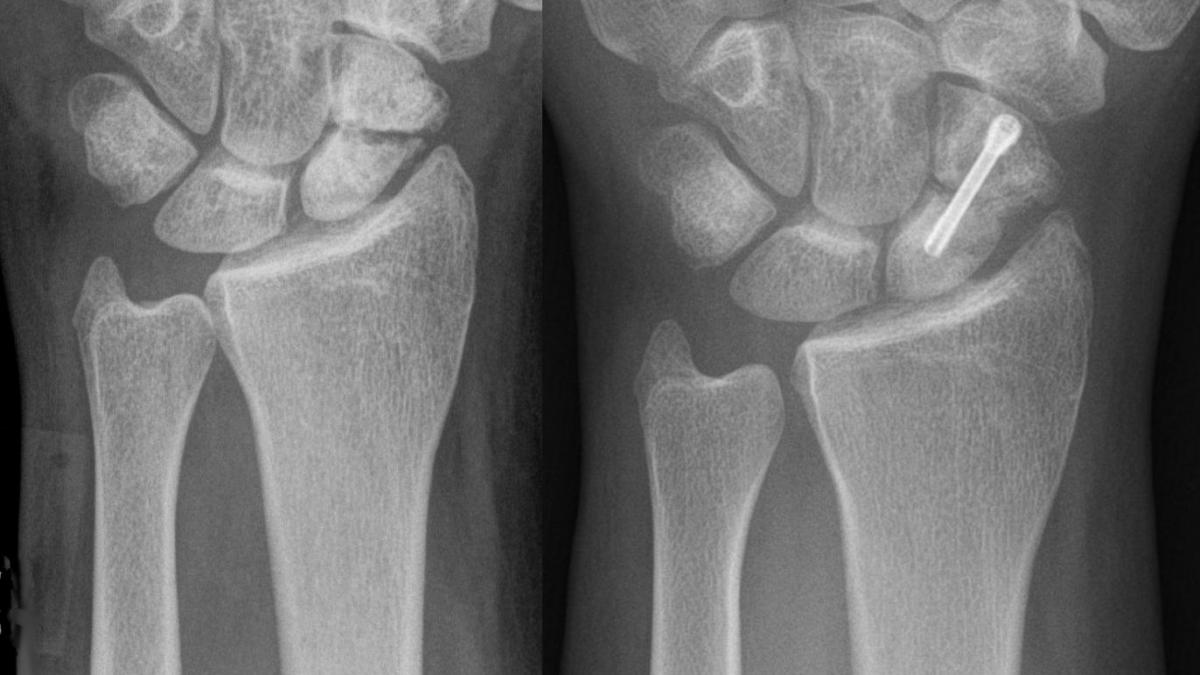

Ученые выявили у него повреждение Монтеджи — перелом локтевой кости с вывихом головки лучевой кости. Несмотря на попытку лечения (вероятно, шинирование), кости срослись неправильно, образовав радиоульнарный синостоз — сращение, полностью лишившее локоть подвижности.

"Это первый известный случай, когда повреждение Монтеджи привело к лучелоктевому синостозу у древнего человека", — отмечают исследователи.